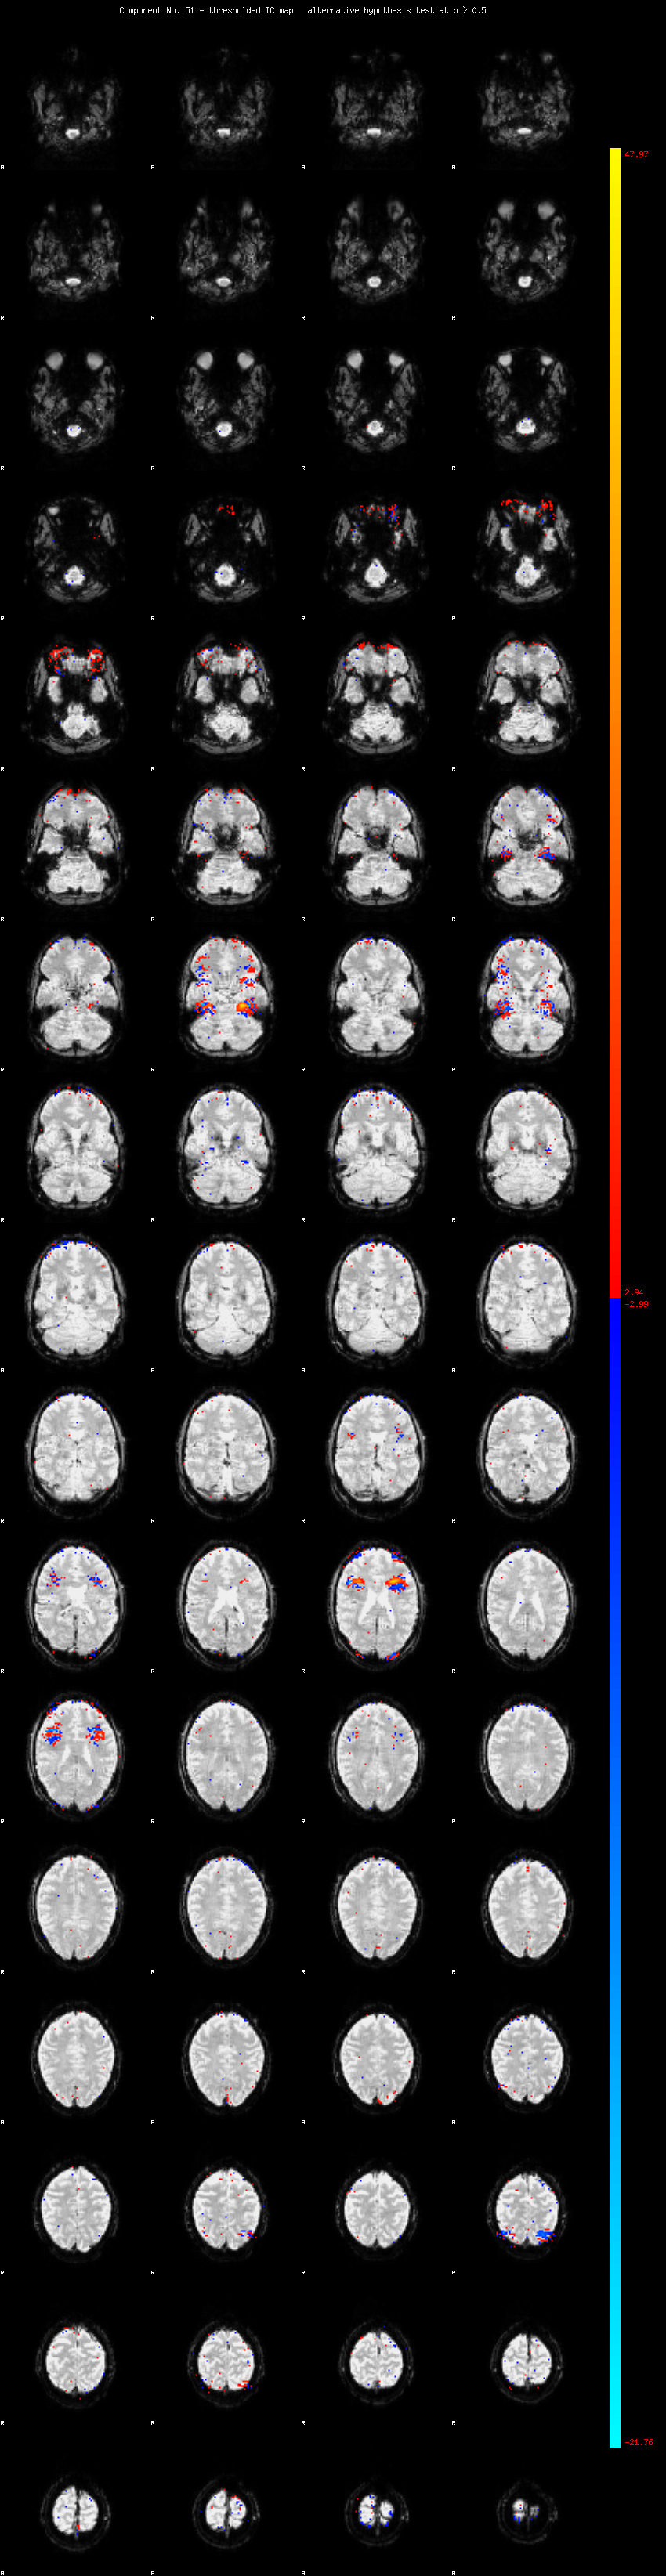

MELODIC Component 51

0.95 % of explained variance;     0.63 % of total variance